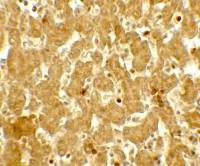

Double immunofluorescence microscopy after staining of mouse embryonic gut tissue with anti-Elastase antibody and anti-Insulin antibody. Tissue sections were prepared using frozen sections after fixation for 1 h in 4% PFA. The image shows elastase staining in green and insulin staining in red. Personal communication, C. Murtaugh, Harvard University